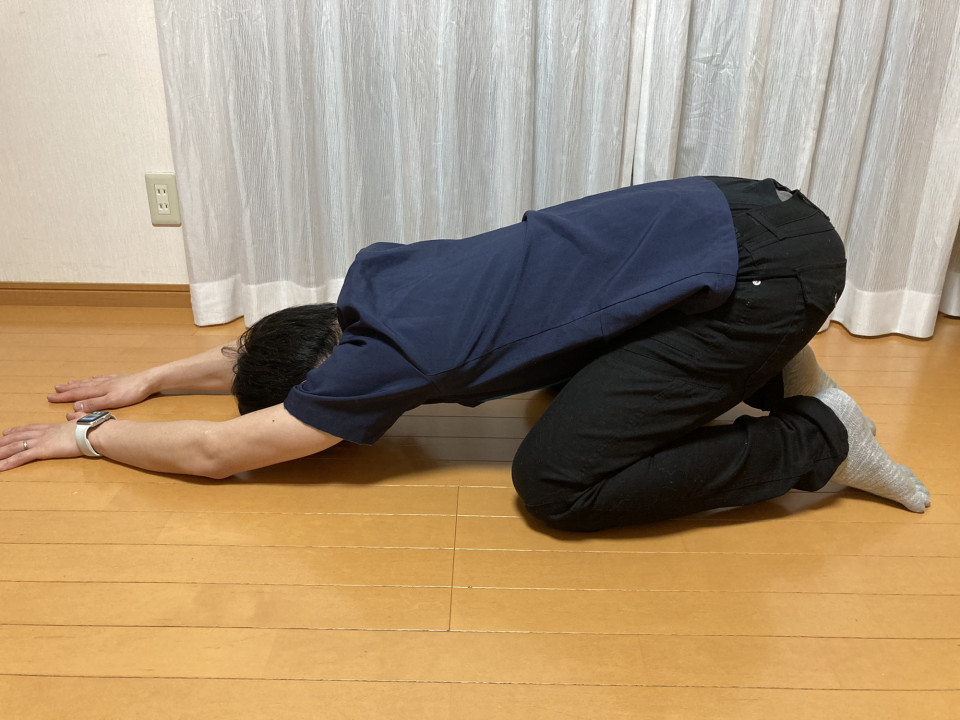

腰痛のセルフケアで必要な2つのストレッチと1つの体幹機能のトレーニングのイメージを載せますので腰痛の方はぜひやってみてください。

1臀部のストレッチ (目安は30秒を3〜5セット)最初は10秒ほどでも良い

2ハムストリングスのストレッチ (目安は30秒を3〜5セット)最初は10秒ほどでも良い

3腹圧をあげてインナーマッスルの活性化 (お腹を凹ませる意識で)

痛みが出る場合は無理に行わず優しくゆっくり時間をかけて行うか、原因が違うこともありますのでやらない方がいい場合もありますのでご自分の体に合わせて行ってください。